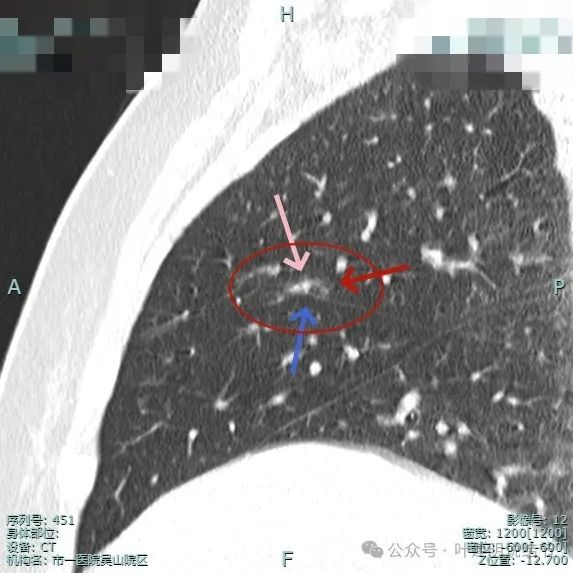

病灶紧贴水平裂,而且水平裂略向病灶侧牵拉,灶内有实性成分。虽然瘤肺边界欠清,但整体轮廓仍显得较为清楚。

混合密度,叶间裂牵拉影响,灶内密度杂乱感。

灶内有小空泡征,表面浅分叶,灶内实性成分明显,有微血管进入病灶。

部分边缘毛刺,边缘区域有磨玻璃成分,有微小血管进入,灶内空泡征。

微血管进入病灶,灶内点状高密度。

叶间裂牵拉向病灶侧,此视角看瘤肺边界较为清楚。